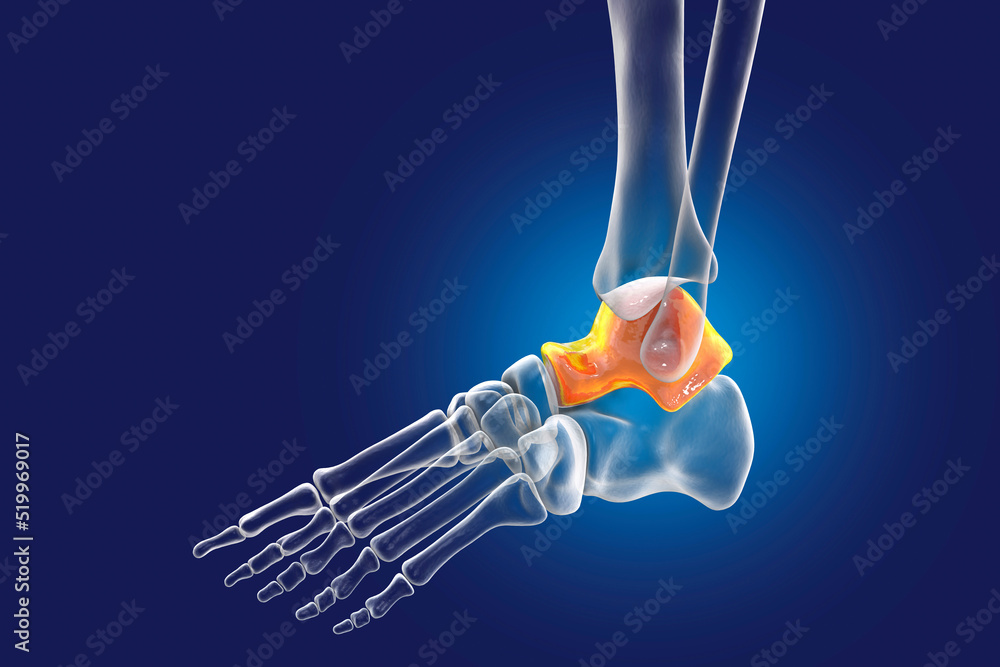

From stock.adobe.com

Human foot anatomy. Talus bone of the foot Stock Illustration Adobe Stock Talus Bone Spur bone spurs often form where bones meet each other — in the joints. The talus bone meets your tibia (shin bone) and fibula (calf bone) to form your ankle joint. Bone spurs on top of your foot. bone spurs, or osteophytes, are bony projections that form along the joints and are often seen in conditions such as arthritis.. Talus Bone Spur.